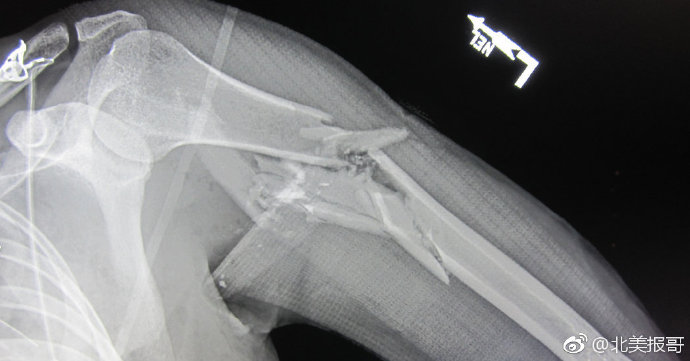

半穿透:*弹子**整体停留在人体内,这样的伤害大于上面那一种,因为*弹子**的动能会对周围部位和器官造成空腔压力损害,同时由于是异物或造成机体感染,当然这也要看是什么类型的*弹子**。没穿透或者穿透留下碎片:这个是最为可怕的,破片是异物或造成机体感染,而且破片方向不定,破口不同,这样的情况发生后,不论是那种*弹子**,击中那个部位,造成的伤害也是最大的。*弹子**击中身体部位首先撕裂的是皮肤肌肉等组织,接着是身体的其他器官或者是血管,造成大剂量失血,器官衰竭而死亡,因此*弹子**击中人体后,不论是哪一个部位,止血我是第一要素。当然以及*弹子**击中人体并不止于此类伤害,还有一个致命的,那就是瞬间造成的空腔效应,虽然这个效应仅仅持续不到一秒钟的时间,但是这个小于一秒钟的伤害是致命的。他会导致机体,神经系统,组织器官永久的伤害,同时*弹子**击中后如果穿透,那么穿透面不论是开不开花的*弹子**的出口都是大于进口的,这样即便是肌肉结缔组织这些都会造成永久伤害。

当然*弹子**击中人体致命步致命要看*弹子**击中人体的时候,他的速度,射击距离,角度,以及击中的部位和伤害程度都有很大的关系 据有效资料可查,虽然*弹子**对于人体造成的伤害基于以上几条之外,还有一个最为重要的因素,那就是*弹子**进入人体后是走直线,斜线,还是乱跳?同时*弹子**是碎裂成小片,大片,还是整体,这些都和弹头的设计有很大的关系。开花的*弹子**击中部位,会造成较大伤口,肌体组织损伤较大,修复困难,这样的伤口失血是非常严重的。死亡的机率也要远远大于一般*用军***弹子**。这也是为什么军事邻域是不允许使用开花弹的,当然警方则不同,警方为了停滞力是必须使用这种*弹子**的,虽然这个在某些方面看来有点“残忍”。

同时*弹子**进入人体后,并不会一个方向,或者是整体不变形,*弹子**往往会碎裂,会在身体内走不规律的路线,从而导致多器官受损,直接导致多器官衰竭。因此一旦*弹子**击中躯干部位,那就只要看你是不是运气好了,我们曾经看到过一个被警用*弹子**连续击中四枪的犯罪嫌疑人,其中一颗击中左臀部的*弹子**竟然从他的右后背腰部以上飞出,而击中右前胸的一颗*弹子**居然从左臂内测飞出同时切断了左臂内存动脉血管,尽管EMS在第一时间就到达,而且带了很多血浆和快速输血器材,但是嫌疑人还是在不到两分钟内就死亡了,这种枪伤其实也基本是没有任何希望的,只不过是早点晚点死亡而已。